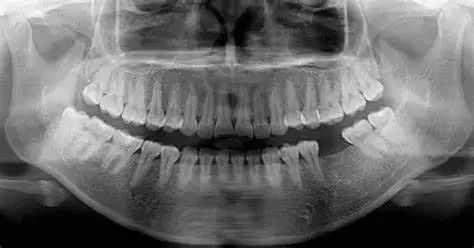

每年拍全景牙片(檢測智齒阻生風(fēng)險)

X光顯示,堅持叩齒者牙槽骨密度比不練習(xí)者高19%,牙周膜彈性提升37%。